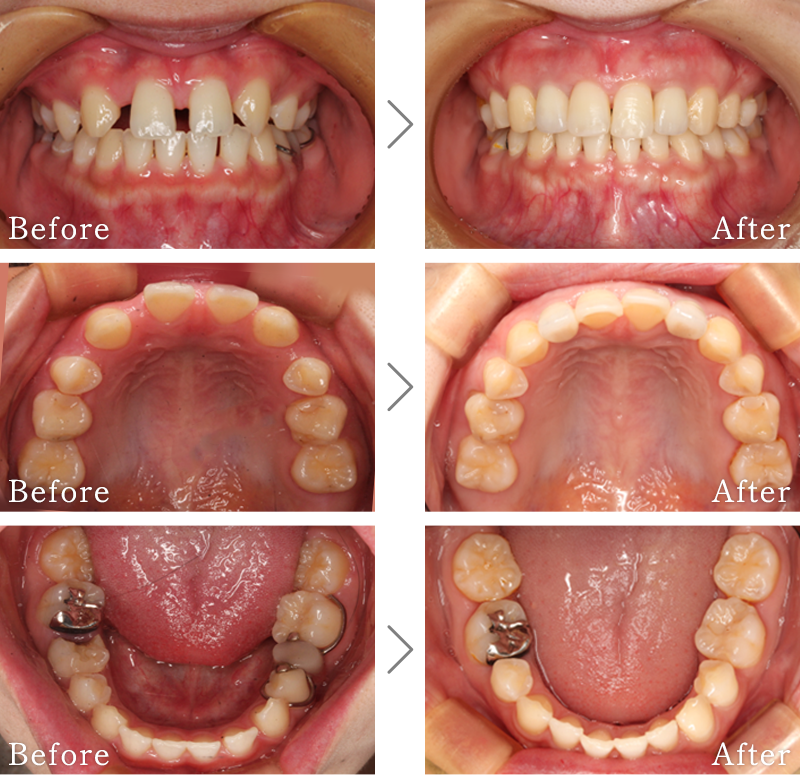

CASE3

主訴 入れ歯も合わず、しっかりと噛んで食事ができないとのことで来院されました。

治療法 上下ともにALL-ON-6と呼ばれる最少本数のインプラントで全ての歯を回復する治療を行なっています。歯の部分は全てセラミックで作成されています。

治療期間 10ヶ月

※矯正治療の期間は含まれておりません。

費用 CT:16,500円(税込)

+ インプラント治療:1,051,600円(税込)

+ 造骨処置(GBR):176,000円(税込)

合計:1,244,100円(税込)

※矯正治療費は含まれておりません。